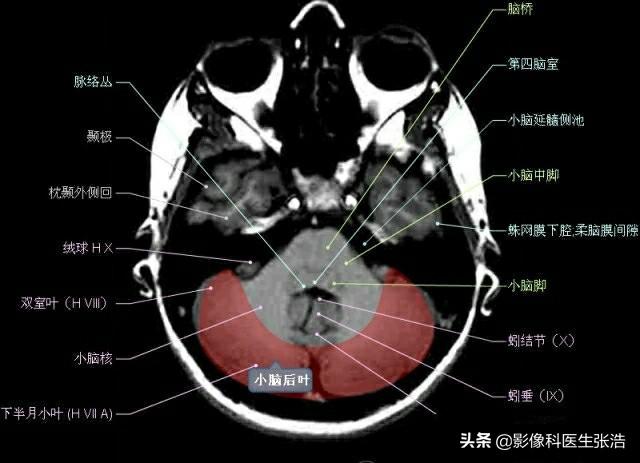

核磁共振(MRI)是一種利用磁場和射頻脈沖來生成身體內(nèi)部結(jié)構(gòu)的詳細圖像的非侵入性檢查技術(shù),頭部核磁共振主要用于檢查腦部疾病、神經(jīng)系統(tǒng)問題以及血管狀況等,這項檢查對于疾病的早期發(fā)現(xiàn)和治療具有非常重要的意義。